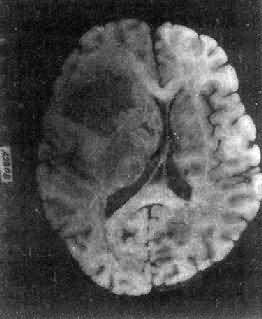

高度恶性的星形胶质细胞瘤称为多形性胶质母细胞瘤(glioblastoma multiforme),多见于成人。肿瘤好发于额叶颞叶白质,浸润范围广,常可穿过胼胝体到对侧,呈蝴蝶状生长(图16-24)。瘤体因常有出血坏死而呈红褐色。镜下,细胞密集,异型性明显,可见怪异的单核或多核瘤巨细胞。出血坏死明显,是其区别于间变性星形胶质细胞瘤的特征。毛细血管明显增生,内皮细胞增生、肿大,可导致管腔闭塞和血栓形成。肿瘤发展迅速,预后极差,患者多在2年内死亡。

图16-24 多形性胶质母细胞瘤

在两半球内肿瘤呈蝴蝶状,边界不清,切面见有出血、坏死及液化